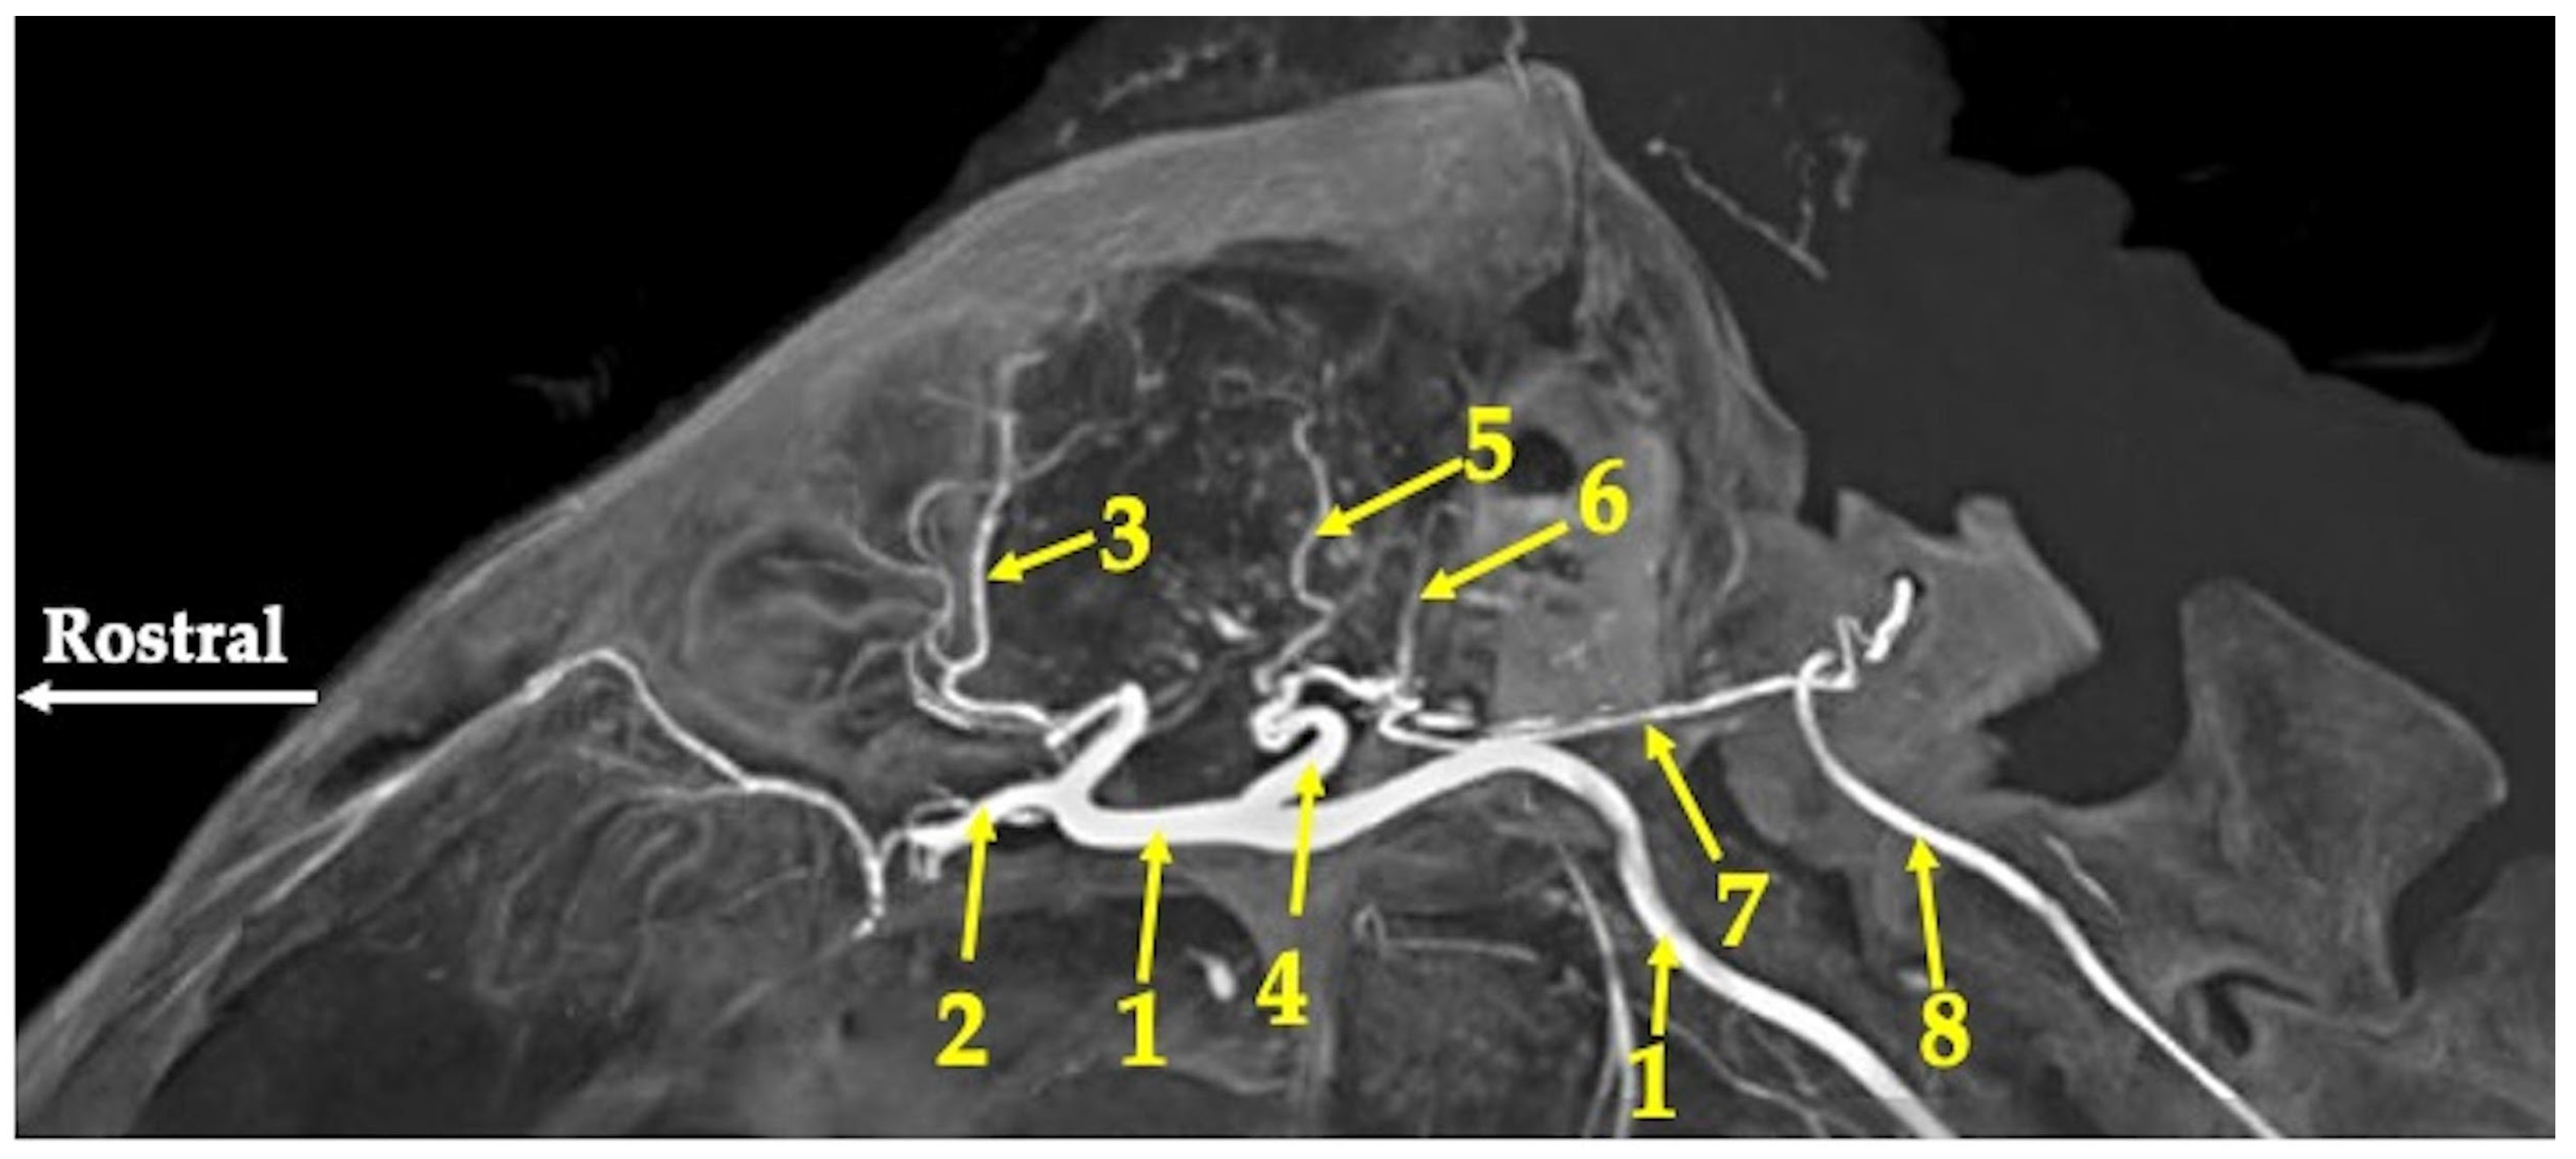

3. Results